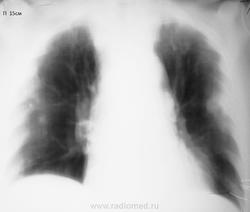

Мужчине 53 года. Госпитализирован в инфекционное отделение с диагнозом: "Лихорадка неясного генеза". Болен 5-й день, 38-39 температура. Снимок обзорный за 16.06 и 2 проекции+томограммы за 27.06. По первому снимку (приемное отделение, заказан обзорный, увидела утром) описала инфильтрацию нижнего легочного поля справа и... плотные старые очаги

. Что скажете коллеги? КТ не работает.

Какая, все-таки, неточная наука, рентгенология. Я бы, по снимку от 17.06. написал бы не инфильтрацию в нижней доле справа, а очаговый процесс (верятнее всего, пневмонию) в верхней доле левого легкого. На снимках от 27.06. отметил бы нарастание процесса, распространение и на верхюю долю правого легкого, заключение: двусторонняя очаговая пневмония, прогрессирующее течение болезни. Обследование на ТВС, конечно же не повредит, но туберкулез обычно так быстро не прогрессирует. А септические эмболы, должны уже были распасться.

Спасибо за комментарии! Перефотографировала, эти картинки мне нравятся больше. Мокроты просто нет, кашля нет.

Мда, томограммы стали определеннее, и на первый план начали выходить объемные образования. Пневмония становится менее вероятной, возрастают шансы метастатического процесса, что не исключает лабораторного обследования на ТВС. У Dr.Drug в прошлом году был случай с лихорадкой и гематогенным распространением, над которым все голову сломали, на секции вроде МТС из тонкой кишки. Кстати, вариант метастазирования первым предложил Валентин Львович.

Менингит. Золотистый стафилококк высеяли в ликворе. Так что второе исследование трактую как септические эмболы. Для полного счастья жду на контроль, обратное развитие увидеть. Центральный распад на некоторых очагах разглядеть можно. Есть и шанс мтс, но невелик.